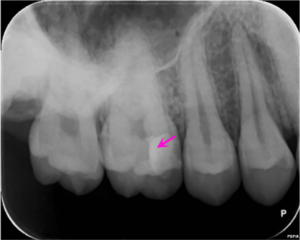

歯髄保存療法1年後のレントゲン写真です。矢印の部分に2次象牙質(歯の神経機能が正常なため神経に穴が開いた部分に自己再生能が働き象牙質が形成され閉鎖していました)が見られました。

電気的な検査で神経は正常でした。

自覚症状は全くありませんでした。